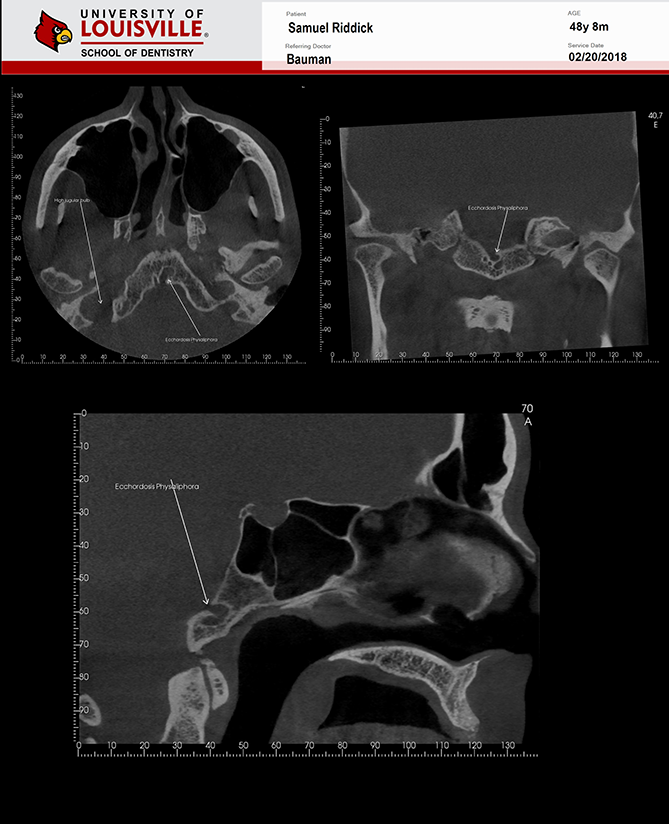

Este é um paciente masculino de 48 anos de idade e foi encaminhado para a clínica de Radiologia oral e maxilo-facial na Universidade de Louisville para uma aquisição de tomografia de feixe cônico da face para planejamento de implante.

Uma tomografia da maxila foi adquirida para avaliação do dente 21 e dos dois seios maxilares. Durante a interpretação do exame foi notado uma área ovalada, multilocular grande, bem definida, corticalizada na região retroclival prepontine. Este achado é fortemente consistente com Ecchordosis Physaliphora. Ecchordosis physaliphora é uma lesão hamartomatosa benigna congênita e pode ser encontrada em qualquer lugar da base do crânio ao osso sacrum. Também notei um forame jugular assimétrico no lado direito. Note que as margens são corticalizadas e não há sinais ou erosão / padrão mordida de traça. O aumento do forame jugular tornando-o assimétrico é fortemente consistente com Bulbo Jugular Alto. Esta variante anatômica ocorre mais comumente do lado direito. Há uma grande e fina espora óssea decorrente da parede lateral esquerda do septo nasal estendendo todo o caminho até a parede lateral esquerda da cavidade nasal.